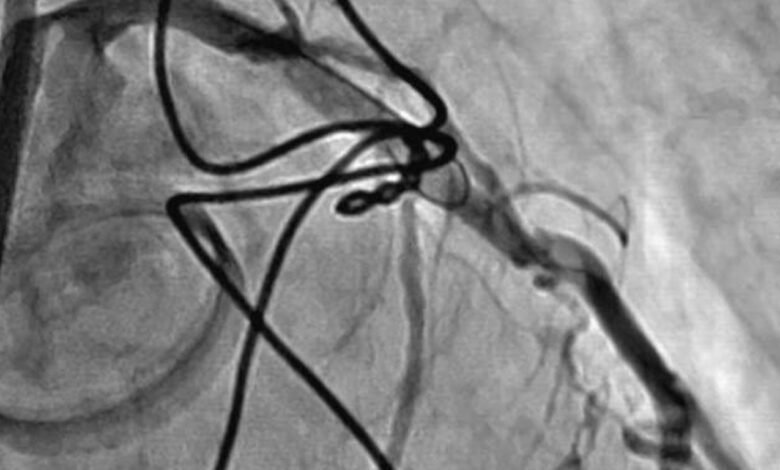

Это заболевание поражает сердце, приводя к воспалению и повреждению клапанов, что в свою очередь может привести к серьезным нарушениям в работе сердечно-сосудистой системы.

1. Нарушение работы сердечных клапанов: Ревматическая болезнь сердца часто приводит к поражению клапанов, что может вызвать их стеноз (сужение) или недостаточность (недостаточное закрытие).

3. Эмболии и тромбозы: Поврежденные клапаны могут способствовать образованию тромбов, которые в дальнейшем могут оторваться и вызвать эмболии в различных органах.